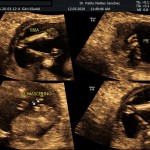

- Las Estructuras Anatómicas Fetales, diagnóstico precoz de Malformaciones (sensibilidad del 80%).